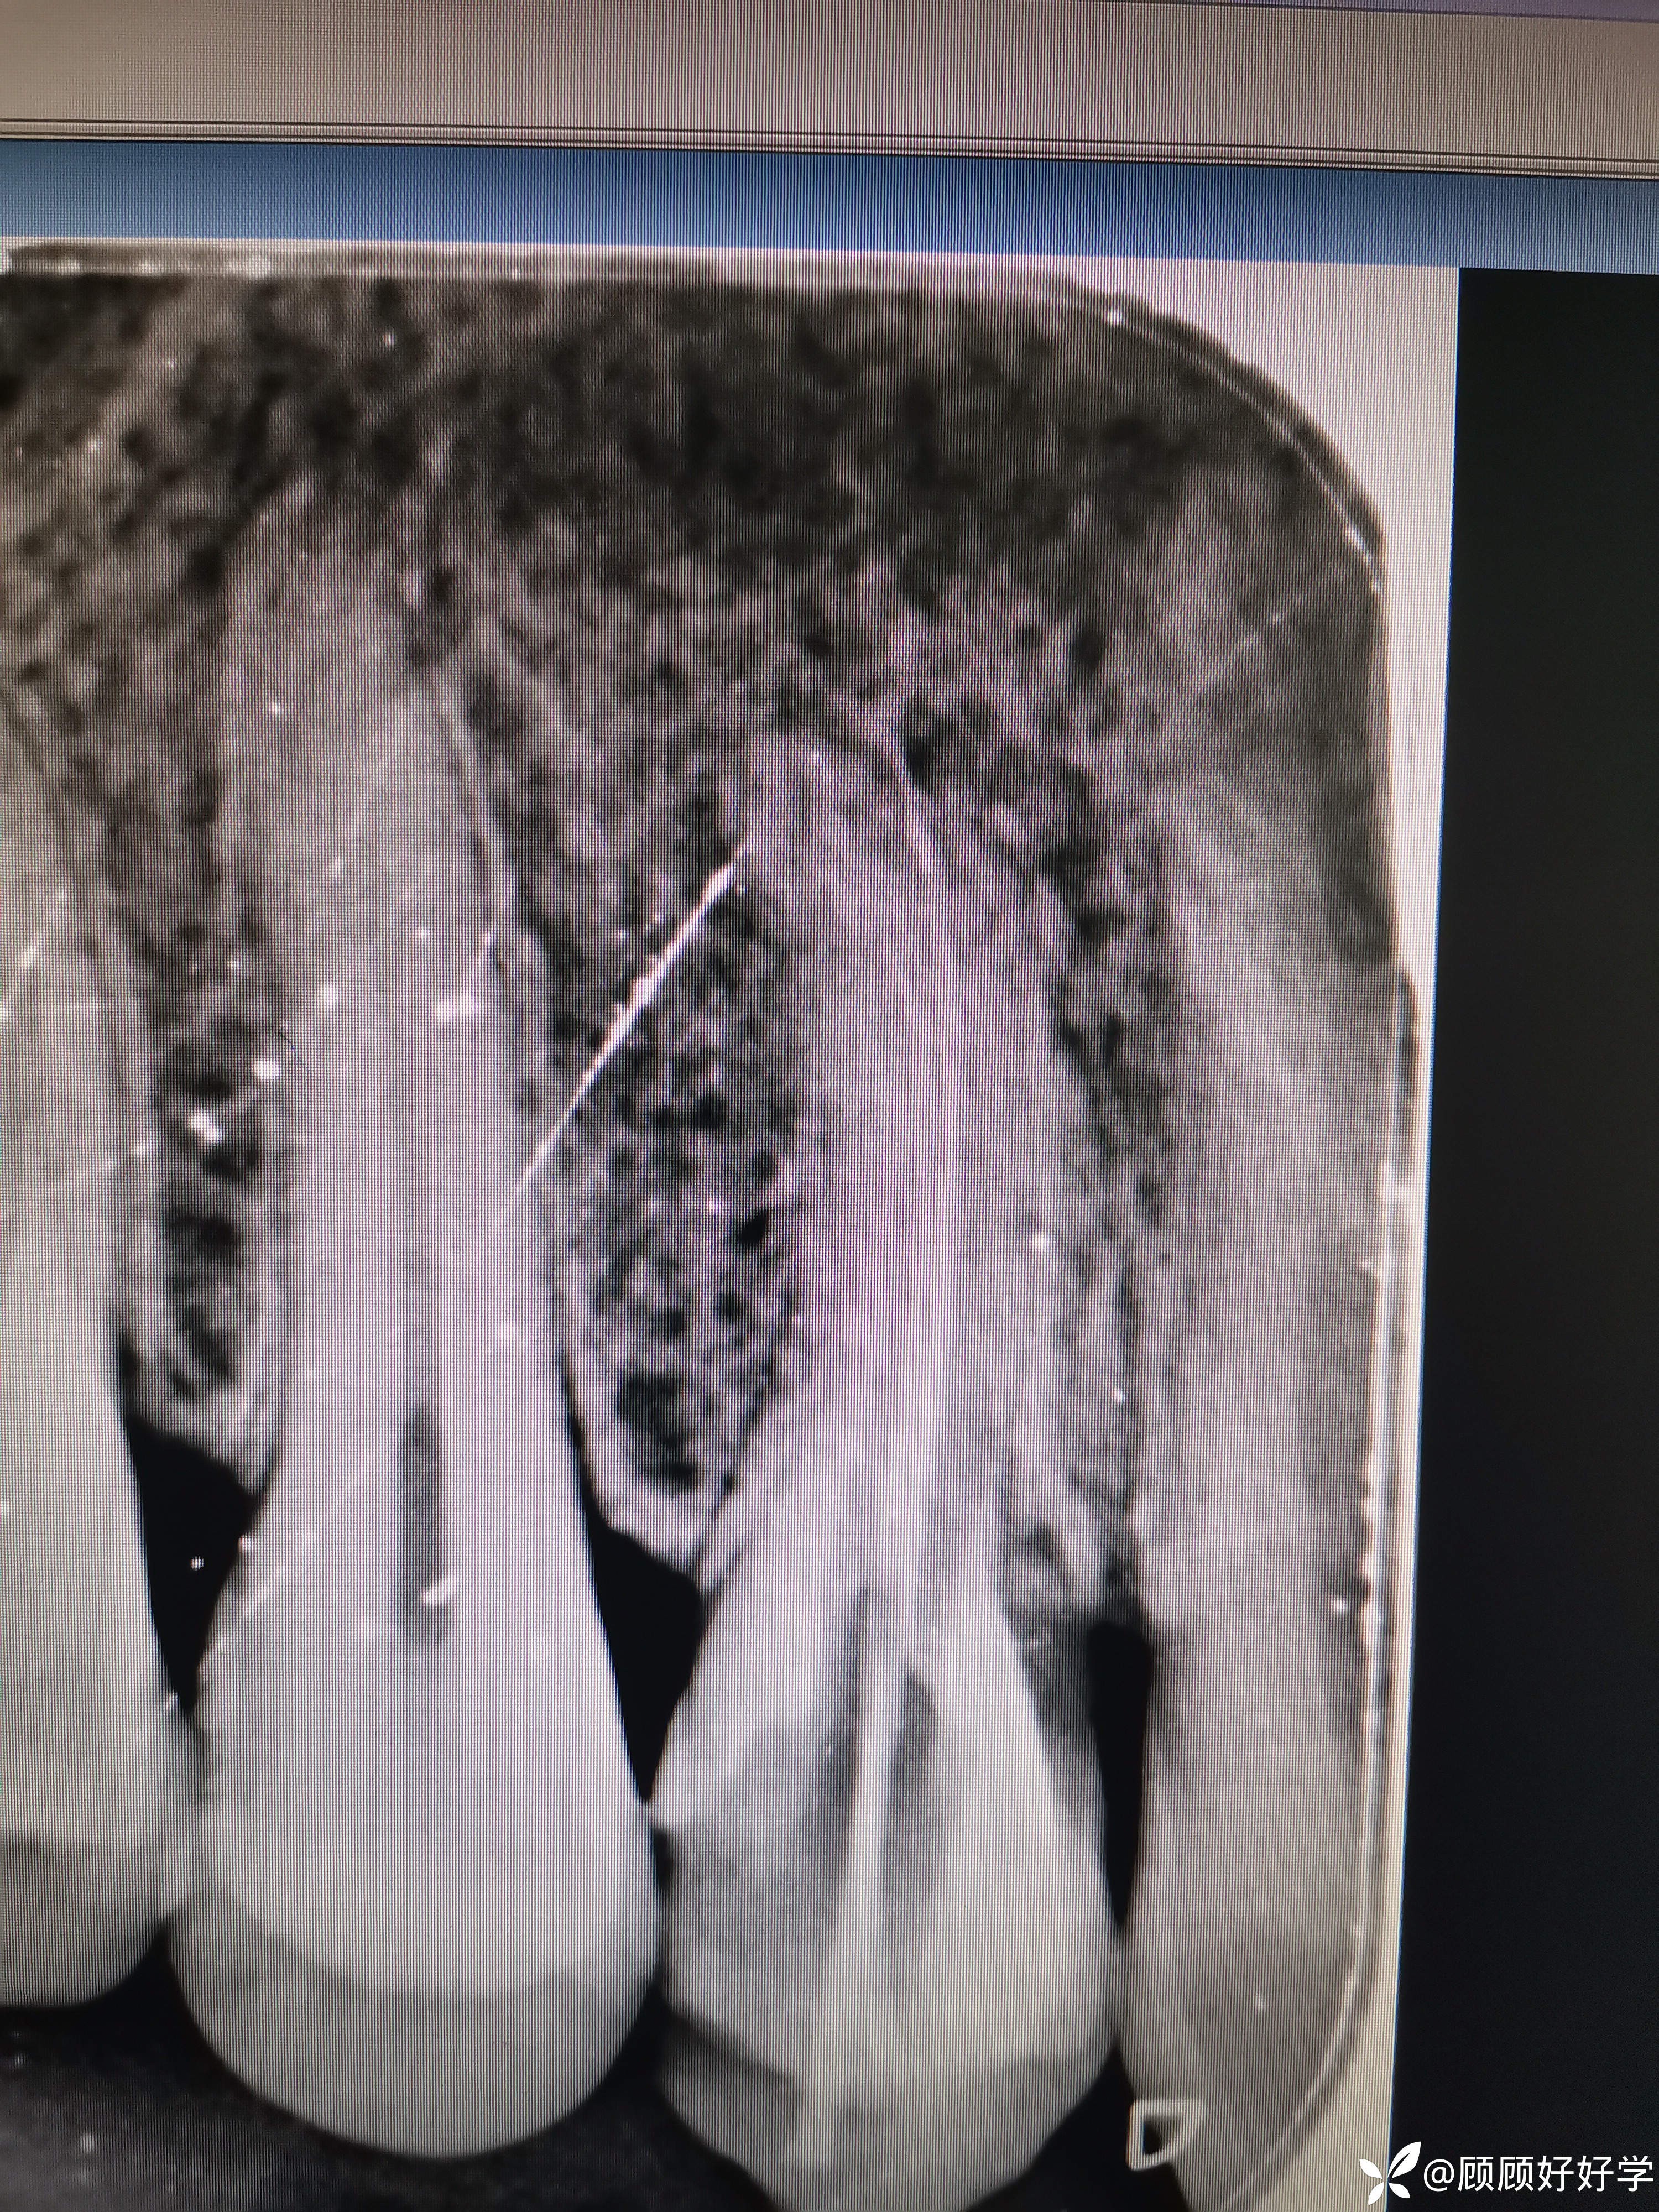

第一次:手扩锉08号K锉疏通颊根至工作长度0.0,记为20mm;10号K锉疏通困难,更换C锉,疏通至根测仪0.0 ,换回10K锉,到达根测仪0.0后取出,发现2mm左右锉尖消失,拍摄根尖片如下

出现器械分离,但10号锉及C锉均可至根测仪0.0,按照经验自觉已经建立旁路;腭根根中1/3下段不同;于是封药,常规医嘱后待下次复诊尝试取出分离器械及疏通腭根。